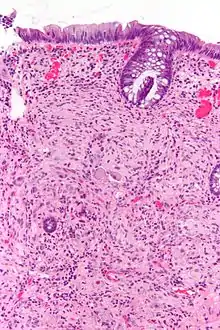

Pathology

Pathologically, ganglioneuromas are composed of ganglion cells, Schwann cells and fibrous tissue.[5] Ganglioneuromas are solid, firm tumours that typically are white when seen with the naked eye.